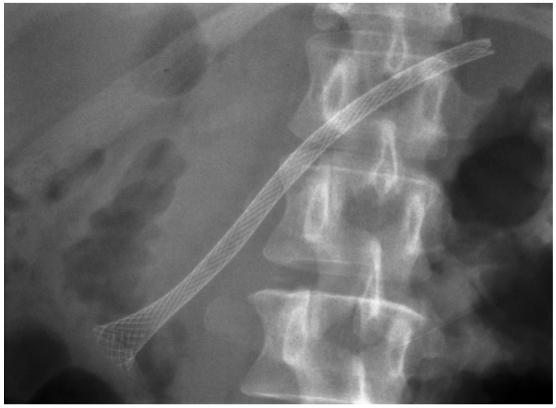

Update on endoscopic treatment of chronic pancreatitis.

Endoscopic therapy has been increasingly recognized as the effective therapy in selected patients with chronic pancreatitis. Utility of endotherapy in various conditions occurring in chronic pancreatitis is discussed. Its efficacy, limitations, and alternatives are addressed. For the best management of these complex entities, a multidisciplinary approach involving expertise in all pancreatic specialties is essential to achieve the goal.

内镜治疗已越来越被认为是慢性胰腺炎特定患者的有效治疗方法。本文讨论了内镜治疗在慢性胰腺炎各种情况下的应用。阐述了其疗效、局限性及替代方案。对于这些复杂疾病的最佳管理,多学科方法(包括所有胰腺专业的专业知识)对于实现目标至关重要。